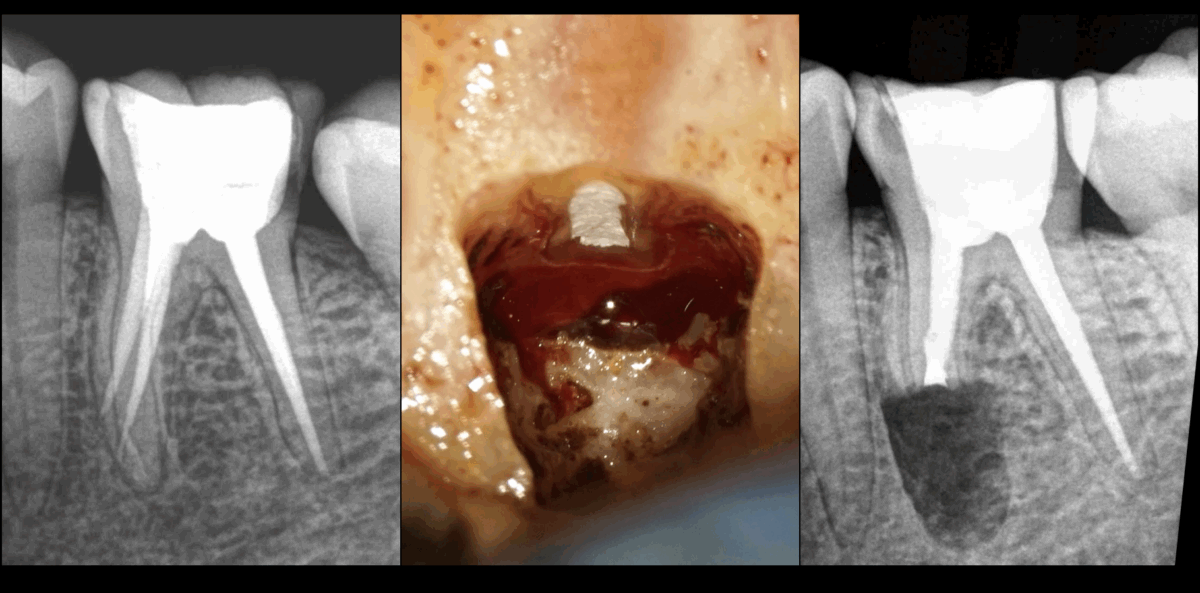

🔍 Une des indications de la 𝐦𝐢𝐜𝐫𝐨𝐜𝐡𝐢𝐫𝐮𝐫𝐠𝐢𝐞 𝐞𝐧𝐝𝐨𝐝𝐨𝐧𝐭𝐢𝐪𝐮𝐞 : la présence d’𝐞𝐫𝐫𝐞𝐮𝐫𝐬 𝐢𝐚𝐭𝐫𝐨𝐠𝐞́𝐧𝐢𝐪𝐮𝐞𝐬 !

Et notamment celles qui manquent de 𝐫𝐞𝐩𝐫𝐨𝐝𝐮𝐜𝐭𝐢𝐛𝐢𝐥𝐢𝐭𝐞́ dans leur gestion 𝐨𝐫𝐭𝐡𝐨𝐠𝐫𝐚𝐝𝐞.

Dans ce cas : la présence de 𝐟𝐚𝐮𝐬𝐬𝐞𝐬 𝐫𝐨𝐮𝐭𝐞𝐬 (voire de 𝐩𝐞𝐫𝐟𝐨𝐫𝐚𝐭𝐢𝐨𝐧𝐬) à la limite 𝟏/𝟑 𝐚𝐩𝐢𝐜𝐚𝐥 – 𝟏/𝟑 𝐦𝐞́𝐝𝐢𝐚𝐧 de la 𝐫𝐚𝐜𝐢𝐧𝐞 𝐦𝐞́𝐬𝐢𝐚𝐥𝐞.